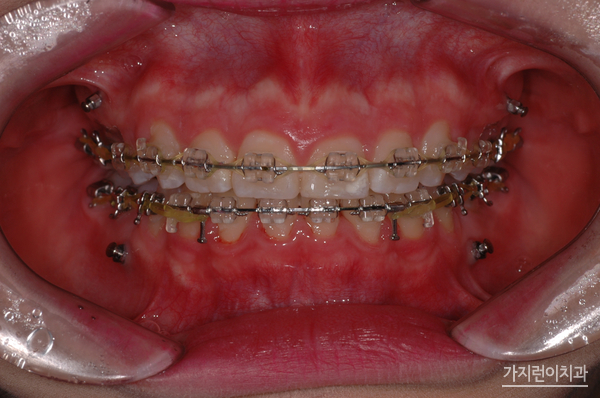

환자 분의 거미스마일과 돌출입 증상은 위 사진과 같았습니다. 치아 돌출은 물론이고 잇몸이 과도하게 나타나는 증상 때문에 스트레스를 상당히 많이 받으셨는데요. 앞으로 나온 부분을 뒤로 집어넣기 위해 상하악 양쪽의 어금니를 발치하였고

미니스크류를 식립해 상악 전치의 후방과 함입 시키는 과정을 진행했습니다. 여기서 말하는 함입과정은 상악 전치를 위로 들어올리는 과정을 말하는데요. 충분한 힘을 주기 위해 미니스크류를 식립했으며

하악에도 미니스크류를 식립해 상하악 전치가 동시에 후방으로 들어갈 수 있도록 조치를 취했습니다. 이런 교정의 과정 끝에 1년 8개월이라는 시간이 소요 되었는데요. 하지만 수술적인 방법 없이 교정만으로도 돌출입교정과 거미스마일 치아교정을 성공적으로 마쳤기에 환자분의 만족도가 높았던 과정이었습니다.